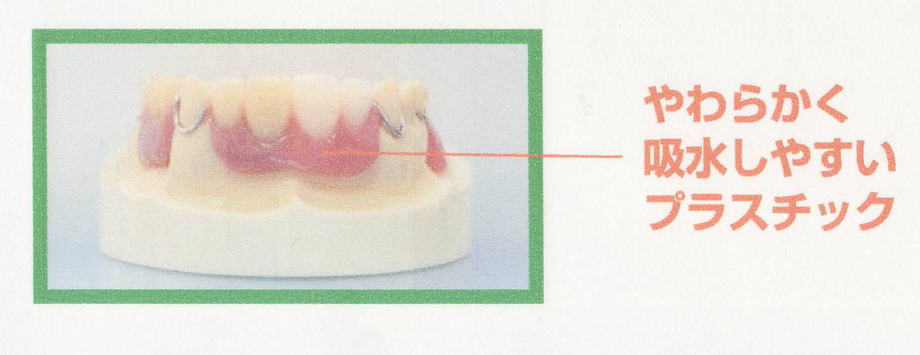

本日、出来上がりました自費の部分入れ歯ー下顎メタルプレートの症例です。

81歳の女性OUさんはとけも若々しいかたで、上下ともに、ぶぶん入れ歯ですが、今回は下顎の左右の奥歯のメタルプレートの入れ歯を新しく作りました。

自費によるメタルプレート義歯で、薄く丈夫な義歯として、とても舌感の良好な状態にすることができ、さらに自由な義歯の設計ができるため、残っているはにかける針金は白金加金で作成し、残存歯にやさしい設計となっており、舌に触れるバー部分はコバルトクロム合金で、丈夫に薄く作ってあります。

(参考代金;30万円)